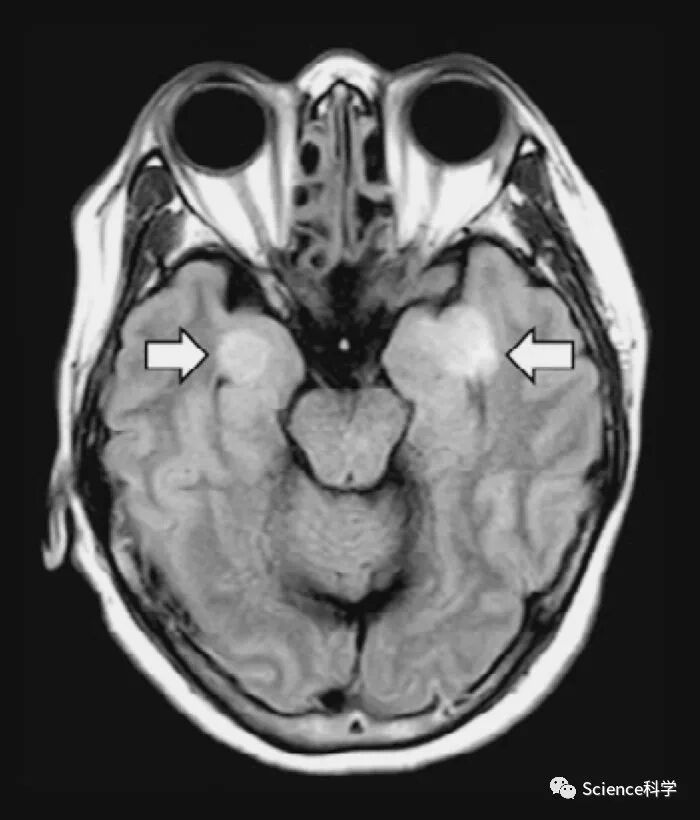

此外,新冠病毒如何影响大脑,是医护人员正在努力解决的另一个主要问题。相当一部分患者出现癫痫发作和脑部肿胀,但目前还不清楚病毒是如何攻击脑干或神经皮层的,而这两个部位都有ACE2受体,病毒可能会附着在这两个部位,也不清楚病毒是否会扩散到保护中枢神经系统许多重要部位的脑脊液。有可能是病毒对血液的影响最终导致了大脑中的反应,因为血块可能会引起肿胀,并引发任何一系列严重的神经系统症状。